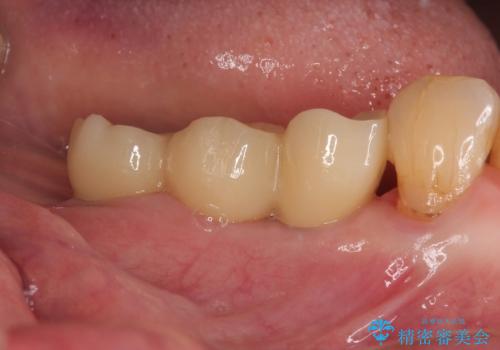

2か月後には無事に値が回復したため、セラミッククラウンにて補綴治療を行いました。

インプラント埋入時に骨とインプラントの安定性を測定し、可能な限り早期に仮歯による咬合回復を図ることを前提に、インプラント補綴治療を行うこととしました。